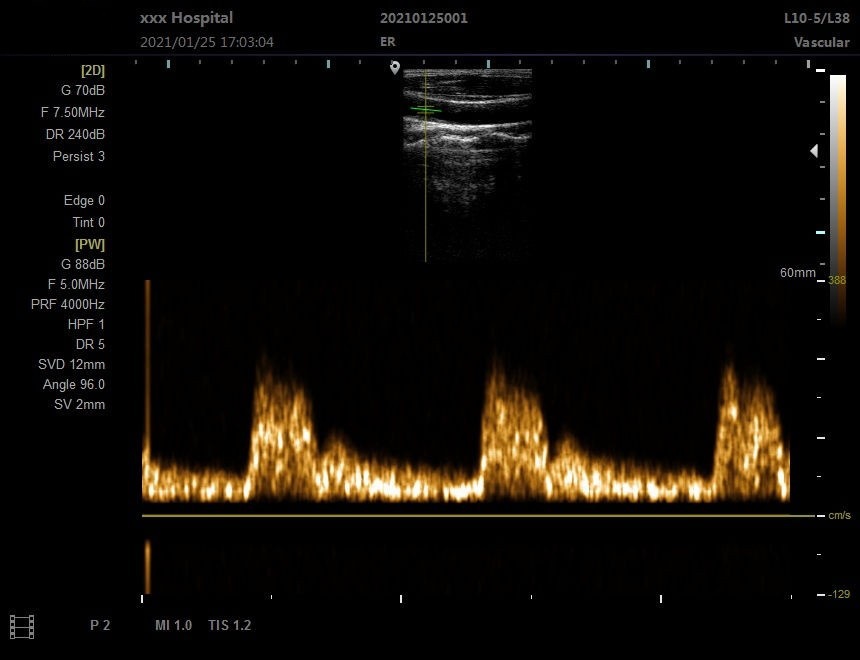

Портативный ультразвуковой аппарат Animal B; Выпуклый массивный зонд; Линейный зонд; Слегка выпуклый зонд; ректальный зонд